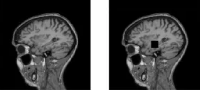

Магнитно-резонансная томография (МРТ):один из самых эффективных методов диагностики заболеваний